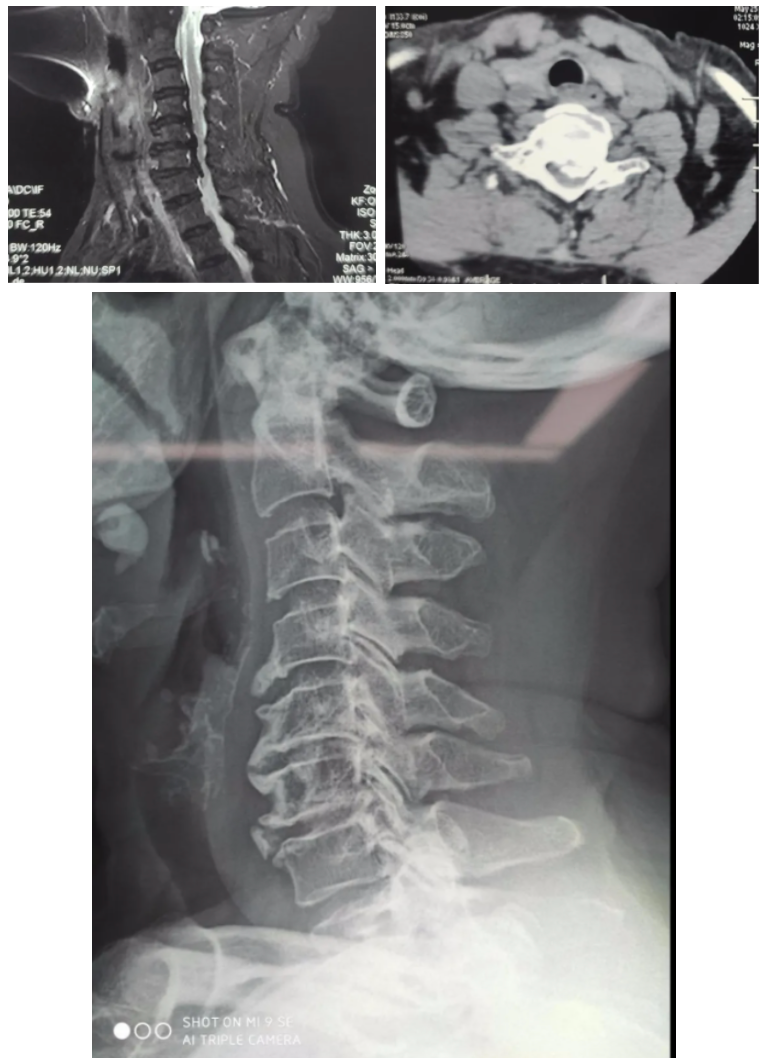

¼Òס¶¨º£µÄ·¶°¢ÆÅ6Äêǰ¾Í×îÏÈ·ºÆðÐÐ×ß¼èÐÁ£¬ £¬£¬£¬£¬ËÄÖ«ÎÞÁ¦×ß·Ïñ½Å²ÈÃÞ»¨£¬ £¬£¬£¬£¬ÒÔΪÊÇÑü×µ¼²²¡£¬ £¬£¬£¬£¬Ê±³£ÔÚ¼ÒÖÜΧµÄÕïËùÐÐÕë¾ÄÍÆÄÃÖÎÁÆ£¬ £¬£¬£¬£¬Ã»Ï뵽֢״һֱδ¼û»º½â£¬ £¬£¬£¬£¬²¢Öð½¥¼ÓÖØ¡£¡£ ¡£¡£¡£¡£¡£3ÄêǰÓÖ×îÏÈ·ºÆðË«ÊÖÂéľ£¬ £¬£¬£¬£¬ÏµØÐÐ×ßÖð½¥ÄÑÌ⣬ £¬£¬£¬£¬ÔÚÍâµØÒ½Ôº¾ÍÕï×öÁ˸÷Ïî¼ì²é£¬ £¬£¬£¬£¬×îºó·¢Ã÷¾¹È»ÊǼ¹ËèÐ;±×µ²¡£¬ £¬£¬£¬£¬±»¼û¸æÏëÒªÖÎÁƵϰֻÄÜ×öÊÖÊõ²Å»ª½â¾öÎÊÌâ¡£¡£ ¡£¡£¡£¡£¡£

×µ¼äÅ̺óÔµ¹ÇÐÔÔöÉúեȡÉñ¾­

ÀîÔº³¤ÏÈÈÝ£¬ £¬£¬£¬£¬¼¹ËèÐ;±×µ²¡ÊÇÓɶàÖÖÒòËØµ¼Ö¾±×µ×µ¹ÜÏÁխեȡ¼¹Ë裬 £¬£¬£¬£¬»¼Õß»á׿¹ËèÊÜѹ¼°±äÐÔµÄˮƽ¼ÓÖØ£¬ £¬£¬£¬£¬Öð½¥·ºÆðË«ÏÂÖ«²ÈÃÞ¸ÐÂéľ·¦Á¦Ë«ÊÖÂéľ·¦Á¦£¬ £¬£¬£¬£¬ºóÆÚÉõÖÁ¿É·ºÆð½ØÌ±¾Þϸ±ãʧ½ûµÈÇéÐΡ£¡£ ¡£¡£¡£¡£¡£·¶°¢ÆÅ¼´ÊÇÓÉ×µ¼äÅ̺óÔµ´ó×Ú¹ÇÖÊÔöÉúեȡ¼¹ËèÒýÆðµÄ£¬ £¬£¬£¬£¬¹ØÓÚÕâÖÖ¹ÇÖÊÔöÉúÑÏÖØµÄ²¡ÈË£¬ £¬£¬£¬£¬¾±×µÇ°Â·ÊÖÊõÎÞ·¨Íê³É¼õѹ£¬ £¬£¬£¬£¬Ö»ÄÜÐо±×µºó·ÈںϼõѹÄÚÀο¿ÊÖÊõ¡£¡£ ¡£¡£¡£¡£¡£